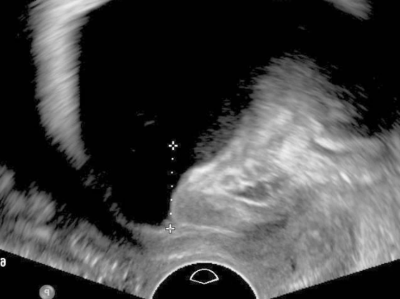

Basisdiagnostik in der Urogynäkologie

Erkrankungen wie Genitalprolaps und Inkontinenz führen oft zu hohem Leidensdruck. Aus Scham sprechen Betroffene jedoch nicht immer über ihre Beschwerden. Dieser Artikel bietet einen Überblick über die gezielte Anamnese und die wichtigsten Untersuchungen in der Urogynäkologie.

Uterosakralligamente /© T. Fink, Chirurgin und Assistentin bei OP/© Georgiy / stock.adobe.com (Symbolbild mit Fotomodellen), Intrauterinpessar aus Kupfer/© Lalocracio / Getty Images / iStock (Symbolbild mit Fotomodell), Gynäkologische Untersuchung mit Spekulum/© Nomad_Soul / Stock.adobe.com (Symbolbild mit Fotomodellen), Intrauterinpessar/© JPC-PROD / stock.adobe.com (Symbolbild mit Fotomodell), Junge Frau sitzt auf Toilette/© Dragana Gordic / stock.adobe.com (Symbolbild mit Fotomodell), Laparoskopischer Eingriff/© RFBSIP / stock.adobe.com (Symbolbild mit Fotomodellen), Netz und Skalpell/© Beate Panosch / stock.adobe.com, Ärztin zeigt auf Modell eines weiblichen Beckens/© H_Ko / Stock.adobe.com (Symbolbild mit Fotomodell), Frau mit Balsenschwäche/© grinvalds / Getty Images / iStock (Symbolbild mit Fotomodell), Beckenbodentraining/© Mathias Ernert, Atelier Gesundheit, Schwangere macht Gymnastik/© fotostorm / Getty Images / iStock (Symbolbild mit Fotomodell), Transvaginalsonographie in der 11+1SSW/© Springer Medizin, Modell einer Levatoravulsion/© Baeßler K et al. / all rights reserved Springer Medizin Verlag GmbH, Magnetresonanz-Defäkographie des Rektums/© Deniz M, Kornmann M / all rights reserved Springer Medizin Verlag GmbH, Ältere Frau mit Trainerin beim Sport/© jacoblund / Getty Images / iStock (Symbolbild mit Fotomodellen), Laparoskopische Operation/© Iryna / stock.adobe.com (Symbolbild mit Fotomodellen), rotatorischer Descensus urethrae mit einem Meatus urethrae internus/© Anzböck T, Koensgen D: doi.org/10.1007/s00117-023-01215-7 unter CC-BY 4.0, Search Icon, Paar schaut glücklich auf Schwangerschaftstest/© Andrii Zastrozhnov / Stock.adobe.com (Symbolbild mit Fotomodellen), ZFA TALKS - Depression/© (M) seb_ra / Getty Images / iStock (Symbolbild mit Fotomodell) Logo: Springer Medizin Verlag GmbH, Ältere Frau fasst sich an die Brust/© Jelena Stanojkovic / Stock.adobe.com (Symbolbild mit Fotomodell), Person setzt DNS-Probe in Maschine ein/© Vit Kovalcik / stock.adobe.com